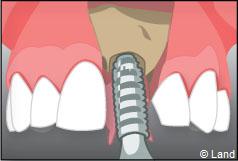

Le chirurgien-dentiste après une anesthésie locale pratique une incision, puis il décolle la gencive pour accéder à l’os alvéolaire.

Ensuite il prépare l’emplacement de l’implant dans l’os en passant plusieurs forets de diamètre croissant. Le forage de l’os se fait à vitesse maîtrisée et lente sous irrigation, pour respecter la structure osseuse et éviter tout échauffement de celle-ci. Le praticien arrête lorsqu’il a obtenu un puits d’un diamètre très légèrement inférieur à l’implant à poser.

L’implant est placé dans l’os le plus souvent par vissage et doit avoir une liaison forte avec l’os. Le praticien replace alors la gencive et pose des points de suture.